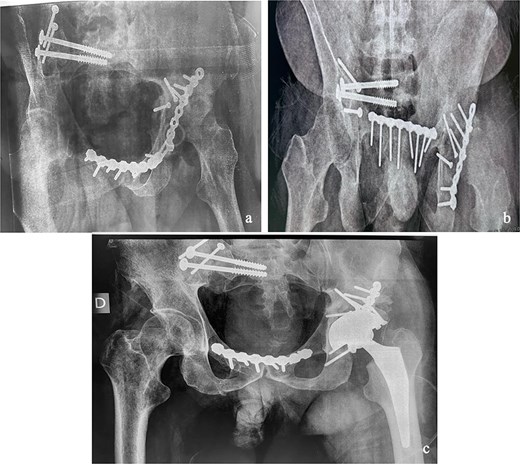

This was a 42-year-old male patient with no previous medical history who was admitted to the intensive care unit for treatment of polytrauma: severe chest trauma and pelvic trauma. During his stay in intensive care, the patient developed a pulmonary infection complicated by septicemia, requiring prolonged antibiotic therapy and thereby contraindicating any internal surgical fixation. After hemodynamic and respiratory stabilization, he was transferred to our department 40 days after the trauma with the following injuries: an unstable pelvic ring fracture classified as Tile-AO B1-2 [4]: disjunction of the pubic symphysis, disjunction of the right sacroiliac joint, and an ipsilateral crescent fracture classified as Kumar-Day 2 [5], along with a transverse–posterior wall fracture of the left acetabulum associated with a posterior dislocation of the hip, which was initially reduced but remained unstable. Fixation was performed using a Hoffmann II external fixator applied to the iliac crests with poor reduction (Fig. 1). He presented with complete weakness of the left foot dorsiflexors, with preserved sensation and no urogenital or abdominal complications. ORIF was performed in two stages, 5 days apart. The first stage consisted of performing the first two windows of the ilioinguinal approach: the lateral window to access the sacroiliac joint and the middle window to access the lower part of the sacroiliac joint and remove the osteofibrous callus. A Pfannenstiel approach was used to remove the callus at the pubic symphysis and fix it with a plate. The patient was then placed in the prone position and a posterior approach to the right sacroiliac joint was performed to carry out the same procedures on the posterior part of this joint and to perform fixation using ilioiliac and iliosacral screws. The second stage of the operation involved acetabular surgery. Given the chronic dislocation of the left hip, an anterior approach to the hip was performed to remove the intra-articular fibrosis facilitating the subsequent reduction of the femoral head. A Kocher-Langenbeck approach was then performed to remove the callus, reduce the femoral head and fracture, and fix it with a plate (Fig. 2). Postoperatively, the patient retained neurological deficits. At 6 months, the patient was able to walk without assistance and had a Harris Hip Score (HHS) score of 80 and Majeed score of 75 [6, 7].

(a) Anteroposterior pelvic X-ray showing delayed pelvic and acetabular fractures. (b) Anterior view of the pelvis on 3D section: pubic symphysis disjunction and right sacroiliac dislocation (arrows), transverse component of the left acetabular fracture (star). (c) Posterior view of the pelvis on 3D section: right crescent fracture associated with right sacroiliac dislocation (circles), fracture of the posterior wall of the left acetabulum associated with posterior dislocation of the femoral head (triangle). (d) Axial section of the pelvic CT-scan: right crescent fracture Kumar-Day 2 (green arrow).